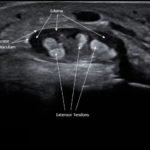

Point-of-care ultrasound of the dorsal aspect of the left hand reveals a heterogenous hypoechoic fluid collection surrounding the extensor tendons (axial view) within the retinaculum consistent with edema. Longitudinal view shows anechoic fluid within the tenosynovium which is located between the anisotropic extensor tendon and linear hyperechoic synovial sheath. Longitudinal view also shows some cobblestoning, or tissue edema, superficial to the anisotropic extensor tendon. The patient’s contralateral right dorsal hand was scanned in a longitudinal view and shows no cobblestoning or hypoechoic fluid under the synovial sheath. The patient was diagnosed with tenosynovitis, and started on intravenous antibiotics.

There is a paucity of literature on extensor tenosynovitis compared with flexor tenosynovitis. The diagnosis of tenosynovitis of the wrist is often clinical using Kanavel’s cardinal signs developed in 1912, though this was developed for flexor, and not extensor tenosynovitis.1 More recently, ultrasound has been used to diagnose tenosynovitis with a sensitivity of 94% and has been shown to be more sensitive than clinical exam.4,5,6 Ultrasound findings may include hypoechoic to anechoic fluid and cobblestoning of the soft tissues, a thickened tendon sheath, and abnormal hypoechoic material within the synovial sheath.5 These ultrasound findings are best seen using a high frequency linear probe oriented in the transverse and longitudinal planes over the dorsal aspect of the hand.6 Our patient’s ultrasound demonstrated cobblestoning of the soft tissues and abnormal hypoechoic material within the synovial sheath; however, we did not measure synovial sheath thickness. While superficial cobblestoning is commonly seen in cellulitis, a thickened synovial sheath and/or abnormal hypoechoic material within the synovial sheath should prompt consideration of tenosynovitis.